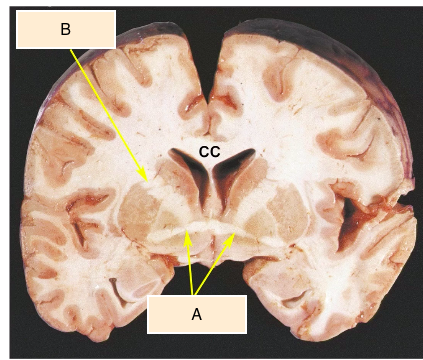

what are A & B? [2]

what do A & B connect? [2]

what are their roles? [1]

A

A = anterior commisure

B = internal capsule

A = temporal lobes

B = lenticular nucleus & thalamus